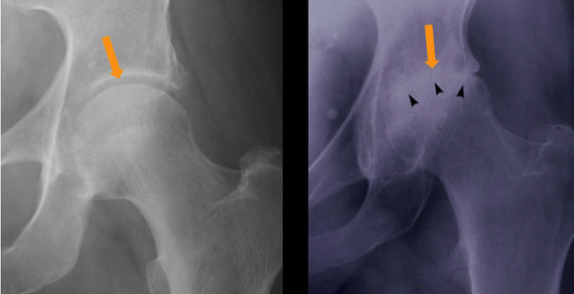

Q

What is shown on this X-ray?

A

Subchondral sclerosis (Black arrows)

Loss of joint space (Orange arrow) in the hip